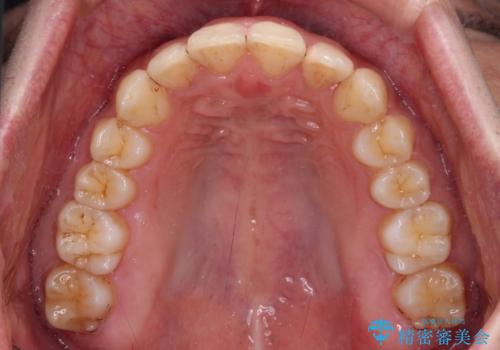

前歯のデコボコをスッキリ改善 インビザライン矯正

- 上下前歯のデコボコを気にして来院された患者様です。

全体的に叢生は軽度であったため、インビザラインにて矯正治療を行うこととしました。

デコボコの改善はもちろん、下顎前歯が隠れてしまうディープバイトも一緒に改善することができ、奥歯への負担を軽減することができました。